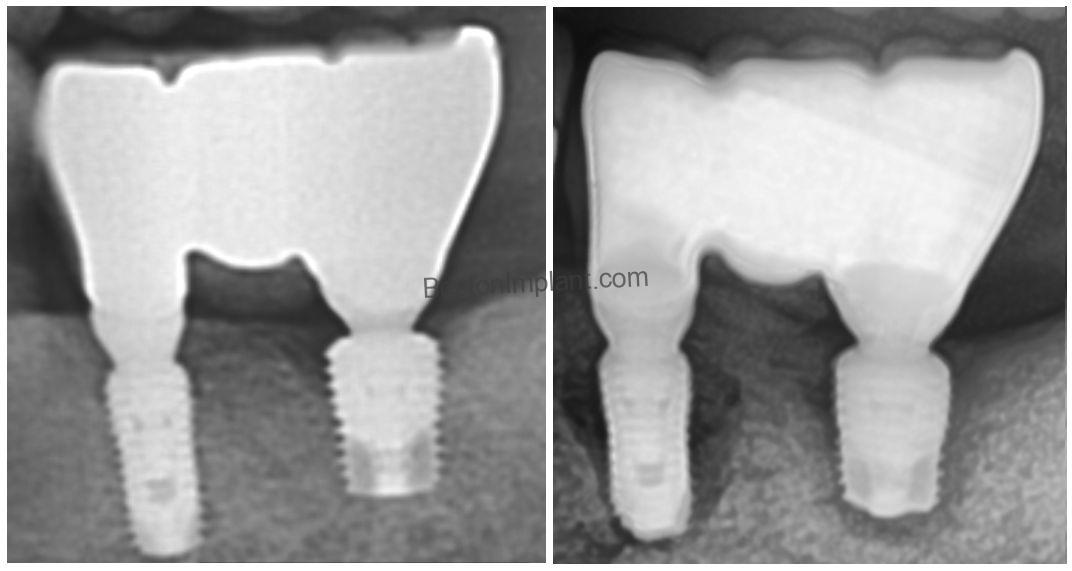

(3) Poor Crown Design (Emergence Profile)

The emergence profile is the contour of the restoration where it emerges from the implant and surrounding soft tissues. It’s influenced by factors such as implant position and the health of the adjacent gums. A well-designed emergence profile should be biologically acceptable (promoting healthy tissues), easily cleanable by the patient, and aesthetically pleasing.

Crown B illustrates a poor emergence profile. Its bulk near the bone area can lead to thin connective tissue. Additionally, the absence of platform switching (a design feature that helps reduce initial bone loss around the top of the implant) can exacerbate bone loss. Over time, Crown B is likely to contribute to bone loss around the implant (as indicated by the change in the green line).

Often, patients with poorly designed crowns don’t recognize the issue initially. It might not be painful, just a mild discomfort. However, this seemingly minor problem can lead to severe complications later on.

HOW TO FIX THIS: In my experience, prioritizing custom abutments is essential for creating an ideal emergence profile. This approach ensures both the long-term structural integrity and the natural aesthetics of the implant restoration.